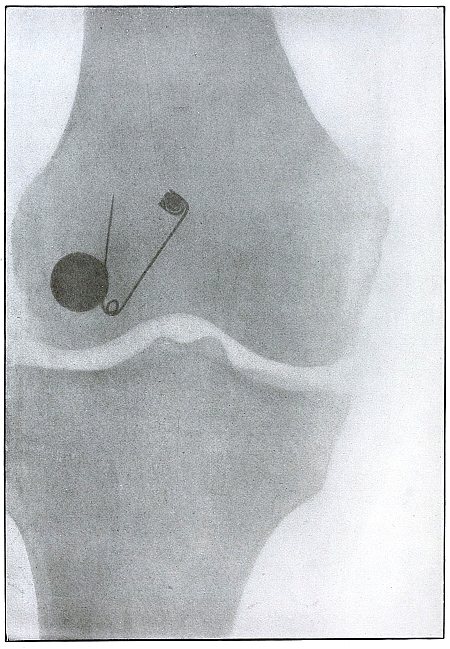

| 59. |

Gunshot wound, knee |

128 |